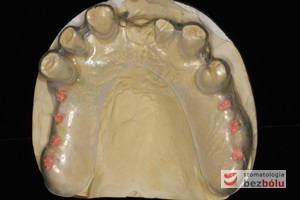

Indywudalizowane filary protetyczne z żywicznymi kluczami - czerwone klucze pattern-resin wyznaczają dokładną pozycję łącznika względem zębów sąsiednich

Indywudalizowane filary protetyczne z żywicznymi kluczami – czerwone klucze pattern-resin wyznaczają dokładną pozycję łącznika względem zębów sąsiednich